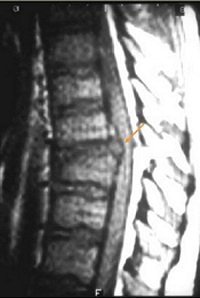

Young gymnasts are particularly susceptible to disk herniation (Neurosurgical Focus online, November 1, 2002, Vol. 13:2). Disk herniation (image G below) in the thoracic spine is more often associated with neurological deficits. Patient management changes with the presence of a disk herniation, El-Khoury said. For gymnasts, delayed or improper treatment can lead to spondylolysis or spondylolisthesis, according to the Lumbar Spine Injuries Laboratory at the University of West Alabama Athletic Training and Sports Medicine Center in Livingston, AL.

![]() |

Image G